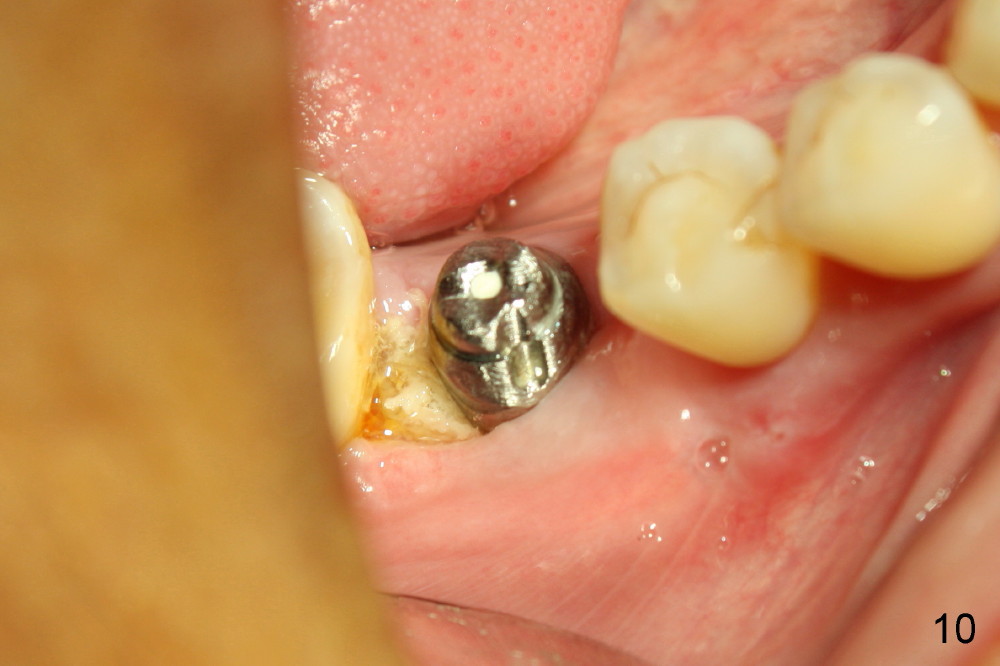

The infection may be related to chronic infection at the tooth #9. The latter is extracted, but the infection at the site of #30 does not resolve (Fig.5,6). The buccal flap is raised to reveal granulation tissue distobuccal to the implant (Fig.7). Bony defect and implant thread exposure are shown after debridement (Fig.8). Irradiated cancellous bone graft is placed to the defect (Fig. 9, Rocky Mountain Tissue Bank). The flap is closed with relative tension free. The definitive crown is temporarily cemented. The graft is exposed with no infection 2 week post grafting (Fig.10). The distobuccal defect appears to have healed 5 months post grafting (Fig.11) and the crown is permanently cemented (Fig.12). There is no buccal bone resorption, probably associated with immediate implantation. The patient remains asymptomatic 13 months postop.